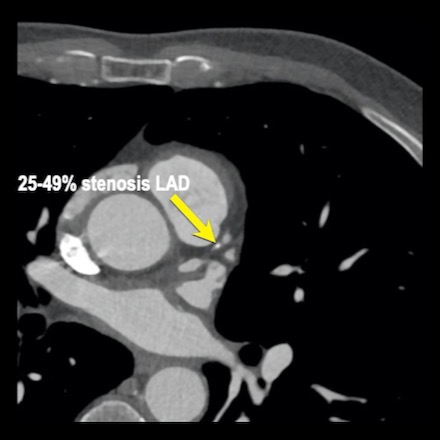

case 1 – CAD-RADS 2/P1

First, scroll through the scan.

Not all images are included. Some images without any abnormalities are skipped

from the series.

How would you describe the findings on the coronary CTA?

The findings are:

- Agatston score of

this patient was 14 (P1). Please, also note the calcification of the aortic valve. - Some partially

calcified and calcified plaques are present in the LAD with mild stenosis

(25-49%). - Calcified-plaque in

the LCX causing minimal stenosis (<25%). - Non-calcified

plaque in the distal RCA causing minimal stenosis (<25%). - This patient classifies

as CAD-RADS 2/P1, which means no further workup is needed.